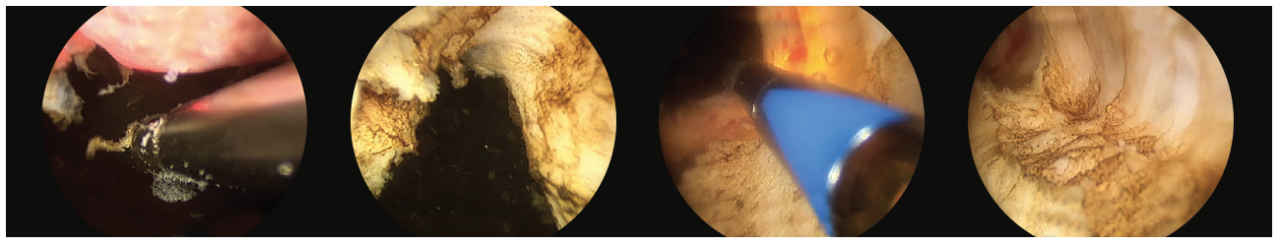

• This is then repeated for both lateral lobes after a 12 o’clock incision is made through the anterior commissure to the capsule and the lateral adenoma tissue are freed off the capsule. (Fig. 4)

4 scope images. Which are illustrating how to debulk the prostate. Figure 4: Incision and release of left sided adenoma.